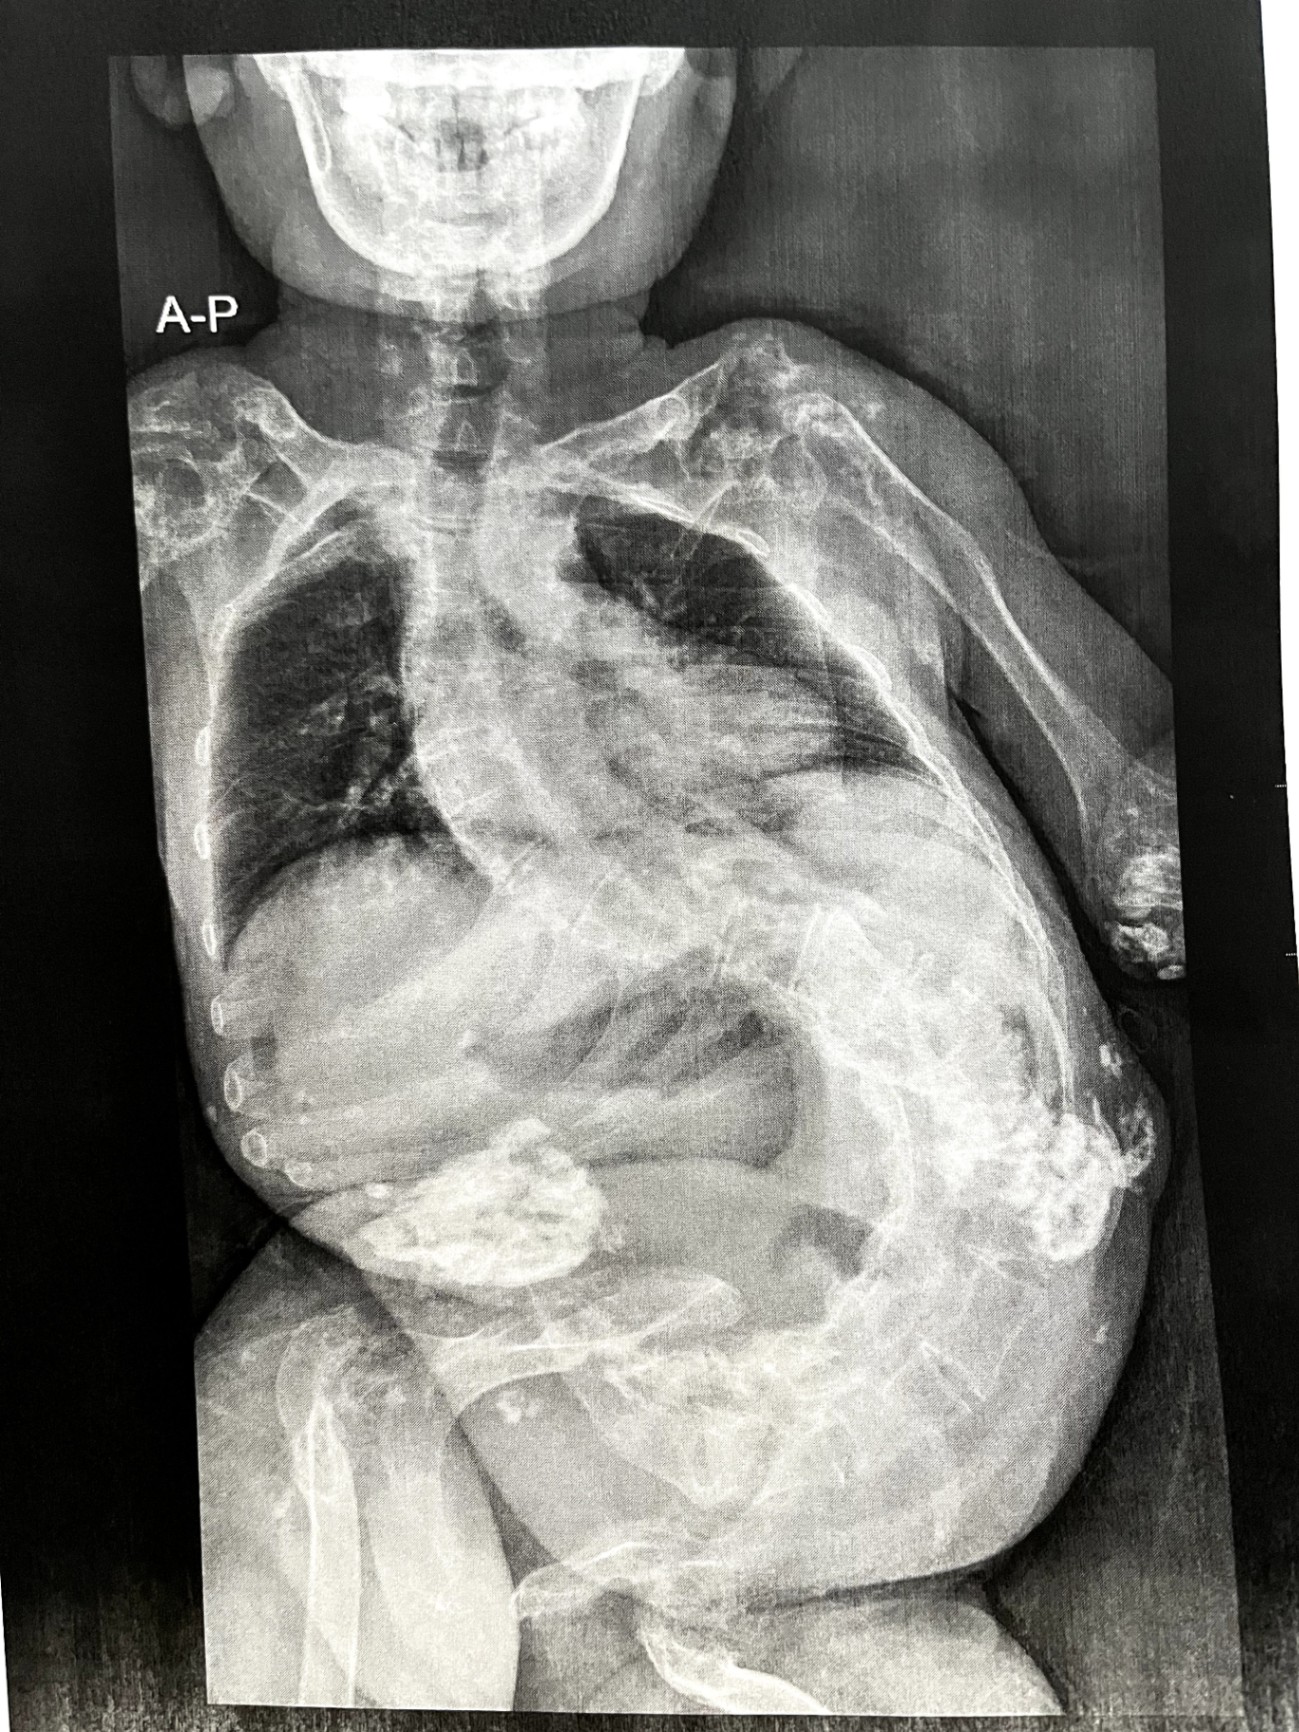

今日はちょっと刺激的な、私の「レントゲン写真」を大公開します!

それがこちら👇

どうですかこの曲がり具合、すごいでしょう。

このように、私は背骨が大きくS字に曲がっています。

また、この曲がった状態で長時間車椅子に座っているため、褥瘡もできてしまいます。